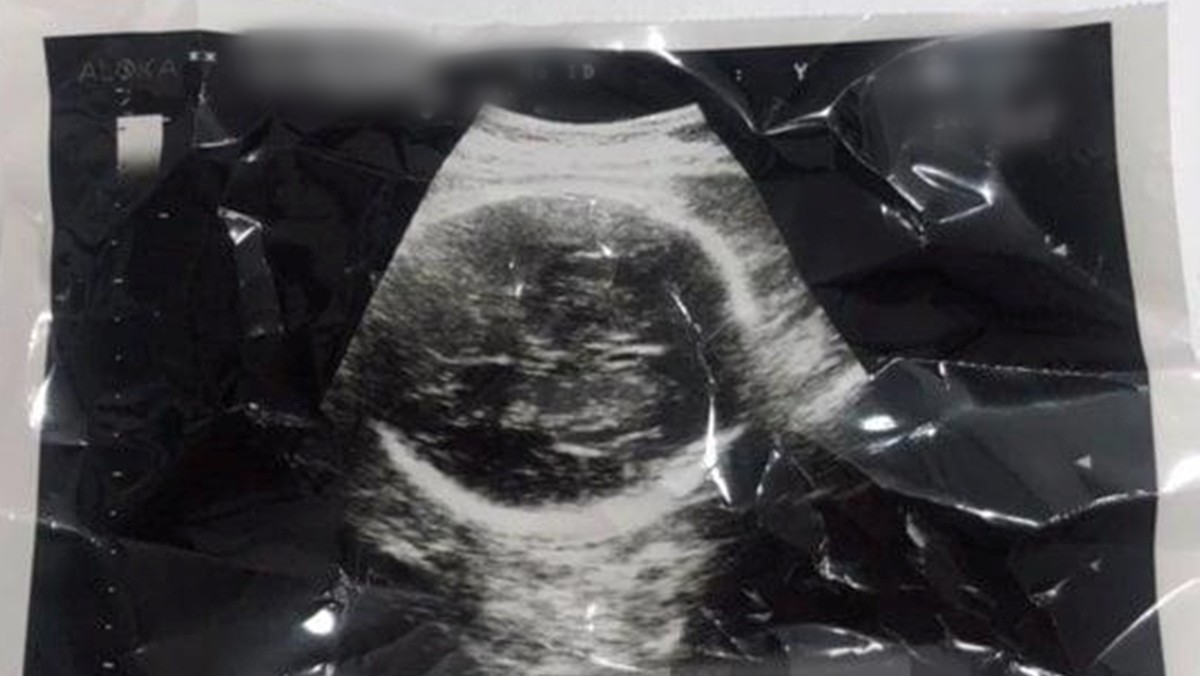

이들은 지난 2024년 6월 임신 34~36주차였던 권씨에 대해 제왕절개 수술을 시행해 태아를 출산시킨 뒤, 사망에 이르게 한 혐의를 받고 있다.